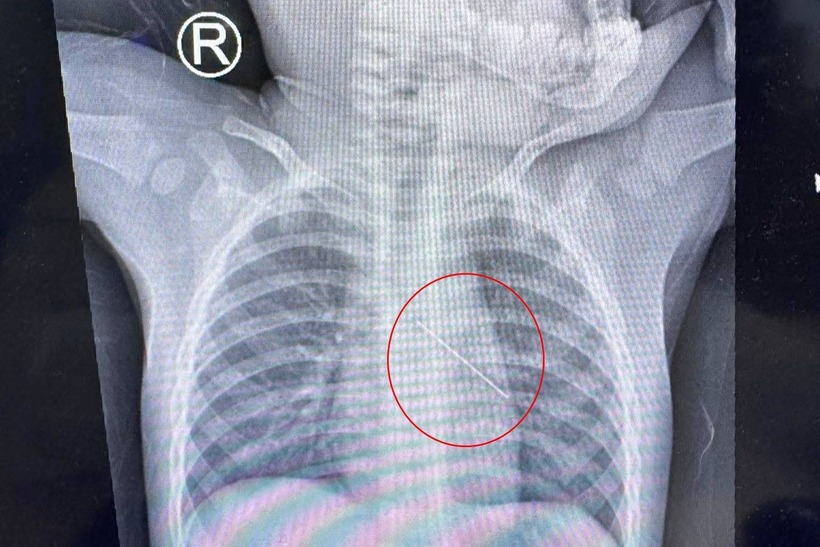

Ảnh chụp X-quang cho thấy kim đâm vào phế quản bé. Ảnh: Dân Trí.

Dân Trí dẫn thông tin từ Bệnh viện Nhi đồng Thành phố (TP.HCM) cho biết, thời điểm xảy ra tai nạn, bé N.M.L. (13 tháng tuổi, ngụ tỉnh Cà Mau) vừa mới biết đi, trên tay cầm một cây kim và đùa giỡn cùng chị trong nhà.

Trong lúc người lớn không để ý, bé bất ngờ sặc mạnh. Cây kim không rơi xuống đất mà đâm sâu vào phế quản, nằm im trong đường thở non nớt của trẻ.

Do dị vật sắc nhọn nằm sâu trong phế quản, trẻ không thể khóc lớn, không kêu đau rõ ràng, chỉ có biểu hiện thở gấp, nguy cơ nghẹt thở. Gia đình lập tức đưa trẻ đi cấp cứu và chuyển viện khẩn cấp từ Bạc Liêu cũ lên Bệnh viện Nhi đồng Thành phố vào sáng cùng ngày.